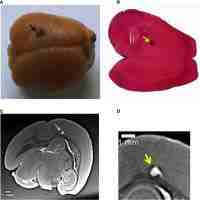

| Abstract | The engineering of large 3D constructs, such as certain craniofacial bone districts, is nowadays a critical challenge. Indeed, the amount of oxygen needed for cell survival is able to reach a maximum diffusion distance of approximately 150 to 200 m from the original vascularization vector, often hampering the long-term survival of the regenerated tissues. Thus, the rapid growth of new blood vessels, delivering oxygen and nutrients also to the inner cells of the bone grafts, is mandatory for their long-term function in clinical practice. Unfortunately, significant progress in this direction is currently hindered by a lack of methods with which to visualise these processes in 3D and reliably quantify them. In this regard, a challenging method for simultaneous 3D imaging and analysis of microvascularization and bone microstructure has emerged in recent years: it is based on the use of synchrotron phase tomography. This technique is able to simultaneously identify multiple tissue features in a craniofacial bone site (e.g., the microvascular and the calcified tissue structure). Moreover, it overcomes the intrinsic limitations of both histology, achieving only a 2D characterization, and conventional tomographic approaches, poorly resolving the vascularization net in the case of an incomplete filling of the newly formed microvessels by contrast agents. Indeed, phase tomography, being based on phase differences among the scattered X-ray waves, is capable of discriminating tissues with similar absorption coefficients (like vessels and woven bone) in defined experimental conditions. The approach reviewed here is based on the most recent experiences applied to bone regeneration in the craniofacial region. |